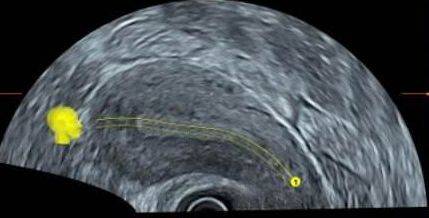

所以胚胎要想着床,子宫内膜很重要,通常,我们把内膜接受胚胎的能力叫做子宫内膜容受性(endometrial receptivity,ER)。临床上有许多指标可用于评估子宫内膜的容受性,但仍缺乏公认的可靠评判标准。目前超声检测因其实时性和无创性的特点,常用于评估ER。